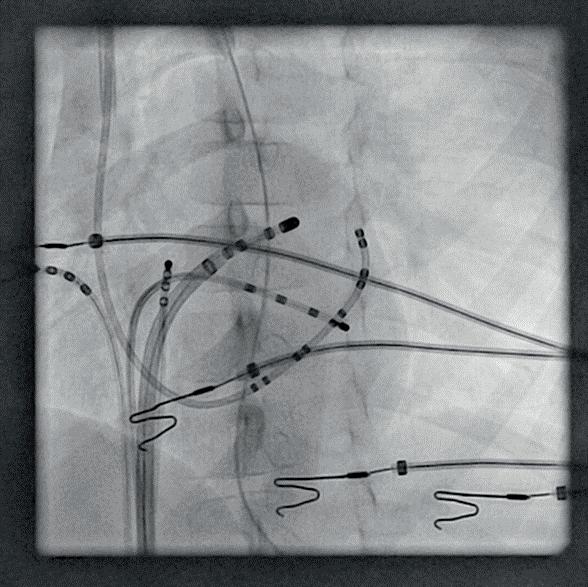

Διουρηθρική εκτομή (transurethral resection of the bladder tumour, TURBT). Συνιστά δι αγνωστική και δυνητικά θεραπευτική μέ θοδο, αφού στοχεύει αφενός στην εκτομή όλων των ορατών όγκων, αφετέρου στη σταδιοποίηση της νόσου. Είναι αναγκαία η πλήρης εξαίρεση του όγκου καθώς και τμήματος του μυϊκού τοιχώματος ώστε να είναι δυνατή η ιστολογική διαπίστωση ενδε χόμενης διήθησης. Σε περίπτωση ατελούς εκτομής, απουσίας εξωστήρα μυός στο πα θολογικό δείγμα – που μπορεί να οδηγήσει σε υποσταδιοποίηση – ή υψηλού κινδύνου νόσου Ta ή T1, συνίσταται η επανάληψη του TURBT εντός 4 έως 6 εβδομάδων. Η ποι ότητα της τεχνικής επηρεάζει τα κλινικά αποτελέσματα. Ενδεικτικά, μια μελέτη κο όρτης σε 1.865 ασθενείς που υποβλήθηκαν σε TURBT διαπίστωσε ότι η υποσταδιοποί ηση κατά την εκτομή συσχετίζεται με χα μηλότερη ειδική για τον καρκίνο επιβίωση [αναλογία κινδύνου (hazard ratio, HR) 1,48, 95% διάστημα εμπιστοσύνης (confidence interval, CI) 1,00-2,18]. ⊲ Κυτταρολογική εξέταση ούρων. Μέσω αυ τής διαπιστώνεται η ύπαρξη καρκινικών κυττάρων στα ούρα. Στηρίζεται στη χαμηλή συνοχή που παρουσιάζουν τα καρκινικά κύτταρα – ιδιαίτερα εκείνα που προέρχο νται από όγκους υψηλού βαθμού κακοήθει ας – με επακόλουθες την αποφολίδωση και ανίχνευση τους στα ούρα. Η κυτταρολογική εξέταση χρησιμοποιείται επικουρικά κατά τη διάγνωση για την ανίχνευση όγκου υψη λής κακοήθειας καθώς και του CIS. Επιπλέ ον, χρησιμεύει στην παρακολούθηση της νόσο μεταθεραπευτικά. ⊲ Απεικονιστικές μέθοδοι. Για τη διάγνωση όγκων του ανώτερου ουροποιητικού χρη σιμοποιείται αξονική ουρογραφία ή εναλλα κτικά ενδοφλέβια ουρογραφία. Σε ασθενείς με επιβεβαιωμένο μυοδιηθητικό καρκίνο, η ύπαρξη μεταστάσεων ανιχνεύεται με τη χρήση αξονικής (computed tomography, CT) ή μαγνητικής (magnetic resonance imaging, MRI) τομογραφίας θώρακος, κοιλίας και πυ έλου. ⊲ Μοριακή διάγνωση. Ογκογόνες μεταλλαγές (πχ. στο γονίδιο FGFR2/3) ή έκφραση βιοδει κτών ανταπόκρισης στην ανοσοθεραπεία (πχ. PD-L1) διερευνώνται στα πλαίσια της

Διαχείριση και θεραπευτικές προσεγγίσεις3,9,10,12 ΜΗ-ΜΥΟΔΙΗΘΗΤΙΚΟ ΟΥΡΟΘΗΛΙΑΚΟ ΚΑΡΚ Ι Ν Ώ ΜΑ Η κύρια θεραπευτική προσέγγιση για το μη-μυοδιηθητικό καρκίνωμα περιλαμβάνει τη διουρηθρική εκτομή (TURBT) ακολουθούμε νη από επικουρική ενδοκυστική θεραπεία με σκοπό τη μείωση των υποτροπών της νόσου: ⊲ Μετεγχειρητική έγχυση χημειοθεραπείας με μιτομυκίνη C, επιρουμπικίνη ή δοξο ρουμπικίνη. Χρησιμοποιείται για χαμηλού κινδύνου ή για επιλεγμένους ενδιάμεσου κινδύνου όγκους. Μία μετα-ανάλυση 7 τυ χαιοποιημένων κλινικών μελετών, έδειξε ότι η ενδοκυστική χημειοθεραπεία μειώνει κατά 39% την πιθανότητα υποτροπής στα επόμενα 3,4 έτη (απόλυτη μείωση από 48% έως 37%). Ωστόσο, δεν υπάρχουν δεδομένα για τη διαφορά στην αποτελεσματικότητα μεταξύ αυτών των φαρμάκων (μιτομυκίνη C, επιρουμπικίνη, δοξορουμπικίνη)

Σε ασθενείς με χαμηλού κινδύνου όγκους, μετά τη διουρηθρική εκτομή, η ενδοκυστική χημειοθεραπεία πραγματοποιείται οριστικά προκειμένου να μειώσει το ποσοστό υπο τροπής. Για τους ασθενείς με ενδιάμεσου κινδύνου όγκους επιλέγεται είτε επαναλαμ βανόμενη ενδοκυστική χημειοθεραπεία είτε ανοσοθεραπεία με BCG για 1 έτος. Στους ασθενείς αυτούς, η ενδοκυστική θεραπεία, παρ’ ότι επιμηκύνει την περίοδο χωρίς υπο τροπή, τελικά δεν αποτρέπει την εξέλιξη της νόσου. Ασθενείς με υψηλού κινδύνου όγκους συνήθως υποβάλλονται σε δεύτερη TURBT και εν συνεχεία σε ανοσοθεραπεία με BCG για 3 έτη. Επειδή το CIS δεν μπορεί να αφαιρεθεί με TURBT, οι ασθενείς με CIS υποβάλλονται απευθείας σε ενδοκυστική ανοσοθεραπεία για 3 έτη. Σε γενικές γραμ μές, η έκβαση της θεραπείας έχει ευνοϊκούς δείκτες επιβίωσης: ενδεικτικά, σύμφωνα με την Αμερικανική Ουρολογική Εταιρεία (American Urological Association, AUA), τα ποσοστά πενταετούς επιβίωσης για τη χωρίς υποτροπή και τη χωρίς εξέλιξη νόσο ανέρχονται αντιστοίχως σε 43% και 93% για όγκους χαμηλού κινδύνου, 33% και 74% για όγκους ενδιάμεσου κινδύνου και 23% και 54% για όγκους υψηλού κινδύνου. Παρ’ όλα αυτά, καθίσταται προφανές ότι ο κίνδυνος υποτροπών είναι υψηλός ανεξαρτήτως του βαθμού κινδύνου. Επιπλέον, ο κίνδυνος εξέ λιξης της νόσου είναι σημαντικός, ιδιαίτερα στους υψηλού κινδύνου όγκους. Με βάση αυτά τα δεδομένα, όλοι οι ασθενείς παρακο λουθούνται τακτικά με κυστεοσκόπηση, ενώ οι ασθενείς με υψηλού κινδύνου όγκους υπο βάλλονται επιπλέον σε κυτταρολογικές εξε τάσεις ούρων και σε αξονική ή ενδοφλέβια